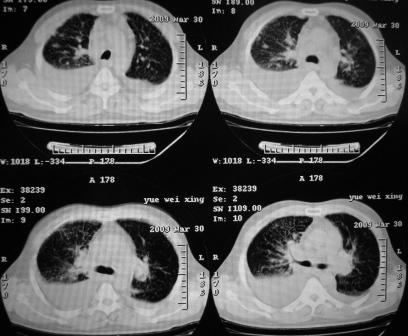

xx 男 43岁

右下叶支气管变窄闭塞,右下叶实变,双肺野弥漫性斑片状影,肺纹理增多增粗,纵隔多发淋巴结肿大,双侧胸水,考虑1双肺继发型结核,右下叶支气管内膜结核,双侧胸水2右下叶中央型肺癌伴右下叶实变,双肺转移,纵隔淋巴转移,双侧胸腔积液3淋巴瘤,请结合病史进一步检查。

病史呢?先考虑----右中央型肺癌继发下叶不张,双肺及纵隔淋巴转移,双侧胸腔积液,心包积液。

不排除---心脏病变所致

右肺下叶支气管中断闭塞,右下肺见不规块影,并胸腔积液,考虑肺中央型肺癌继发下叶不张,\\双侧胸腔积液,心包积液。

考虑右中央型肺癌并下叶不张,双侧胸腔积液,心包积液

右侧中央型肺癌伴右肺下叶不张,双肺及纵隔淋巴转移,双侧胸腔积液,心包积液。

1)考虑右侧中央型肺癌伴右肺下叶不张,双肺及纵隔淋巴转移。2)双侧胸腔积液,以右侧为甚。3)心包积液。